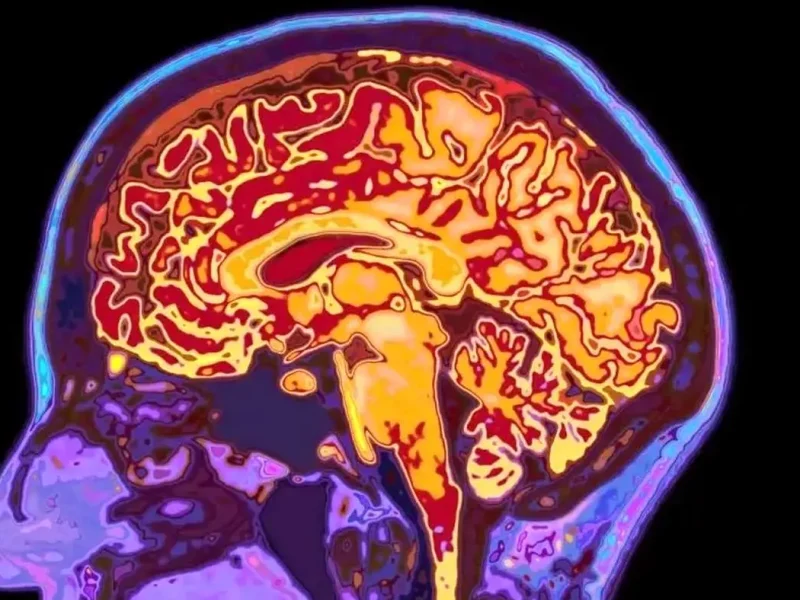

شاید فکر کنید با تمامشدن دوران نوجوانی، مغز شما هم به بلوغ و رشد نهایی رسیده است. اما دانشمندان دانشگاه کمبریج این باور قدیمی را رد کردهاند. آنها با اسکن مغز ۴ هزار نفر (از نوزاد تا ۹۰ ساله) کشف کردند که مغز انسان نه یک مسیر خطی، بلکه ۵ دوران متمایز را طی میکند. محققان میگویند مغز ما تازه در اوایل دهه ۳۰ زندگی وارد فاز بزرگسالی میشود.

تصور رایج این است که نوجوانی در ۱۸ یا ۱۹ سالگی تمام میشود، بااینحال مطالعه جدید نشان میدهد که مغز تا حدود ۳۲ سالگی همچنان در فاز «نوجوانی» باقی میماند. در این دوران طولانی (از ۹ تا ۳۲ سالگی) مغز مشغول سیمکشی مجدد و افزایش بهرهوری است. این همان زمانی است که بیشترین خطر بروز اختلالات سلامت روان وجود دارد، زیرا مغز درحال تغییرات بنیادین است.

به گزارش گاردین، دانشمندان مراحل رشد مغز را براساس ۴ نقطه عطف مهم (در سنین ۹، ۳۲، ۶۶ و ۸۳ سالگی) تقسیمبندی کردهاند:

- کودکی (تولد تا ۹ سالگی) : دورانی که مغز به سرعت رشد و اتصالات اضافی را هرس میکند.

- نوجوانی ( ۹ تا ۳۲ سالگی) : طولانیترین فاز رشد که در آن شبکههای عصبی کارآمد و سریع میشوند. این دوران اوج عملکرد شناختی است.

- بزرگسالی ( ۳۲ تا ۶۶ سالگی) : دوران ثبات که در آن مغز وارد حالتی پایدار میشود. سرعت تغییرات کاهش مییابد اما بهرهوری همچنان بالاست.

- پیری زودرس ( ۶۶ تا ۸۳ سالگی) : شروع کاهش اتصالات مغزی است. مغز کمکم از حالت یکپارچه خارج و به نواحی مجزا تقسیم میشود.

- پیری دیررس ( ۸۳ سالگی به بعد) : مرحله نهایی که تغییرات ساختاری و زوال ماده سفید مغز شدت میگیرد.

در این چرخهها سن ۳۲ سالگی اهمیت بسزایی دارد، چون زمانی است که مغز بالاخره آرام میگیرد. دکتر «الکسا موزلی» (Alexa Mousley)، محقق ارشد این پروژه، میگوید: «درست است که ما در ۳۲ سالگی مثل نوجوانان رفتار نمیکنیم، اما الگوی تغییرات مغزی تا این سن مشابه نوجوانی است.» اتفاقات مهم زندگی مانند پدرومادر شدن یا تثبیت شغلی که معمولاً در این سنین رخ میدهند، احتمالاً با این تغییر ساختاری مغز هماهنگ هستند.